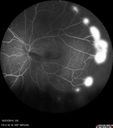

28 year old man who thought he had sickle trait but blood test showed he had HgB SC disease. He had recurrent episodes of vision loss in the left eye and presented with a vitreous hemorrhage. Vision 20/12 OD, 20/25 OS. He had foveal thinning on OCT oS and peripheral NV in both eyes. The left eye was lasered the following week.

Sickle Retinopathy - Ultra Wide Field Angiogram - Heidelberg521 viewsLeakage from peripheral fronds of NV - HGB SC disease - 28 year old man with vision loss OS from acute vitreous hemorrhage00000